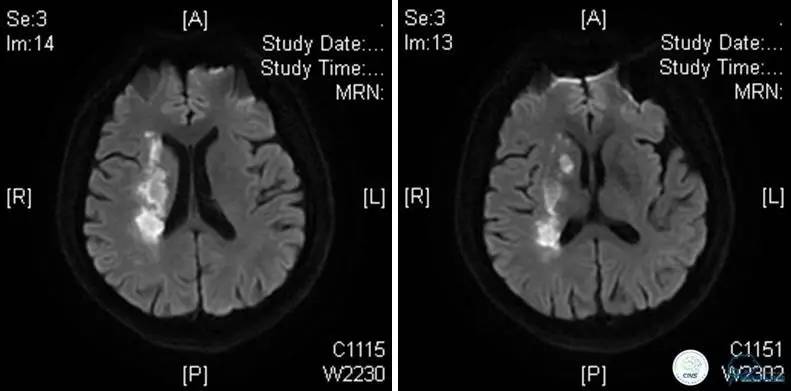

病例5

患者:49岁男性,左侧偏瘫1个月,药物治疗、康复训练效果不好,转我院,肌力0~1级。

core-clilnical明显不匹配,是介入开通的合适患者。

造影评价血管、判断闭塞段,微导丝小心穿过闭塞段,微导管造影,交换技术,球囊扩张,Enterprise支架。在后扩张时导丝刺破M3段血管,蛛网膜下腔出血(SAH)。

微导管进入破裂血管,栓塞弹簧圈1枚,出血停止,结束手术。继续双抗,术后2天肌力2级,神经功能恢复明显加快。

术后即刻和6天后CT,患者无明显临床症状。

半年后复查造影,无支架内再狭窄,可见弹簧圈,患者恢复至自己柱杖行走。